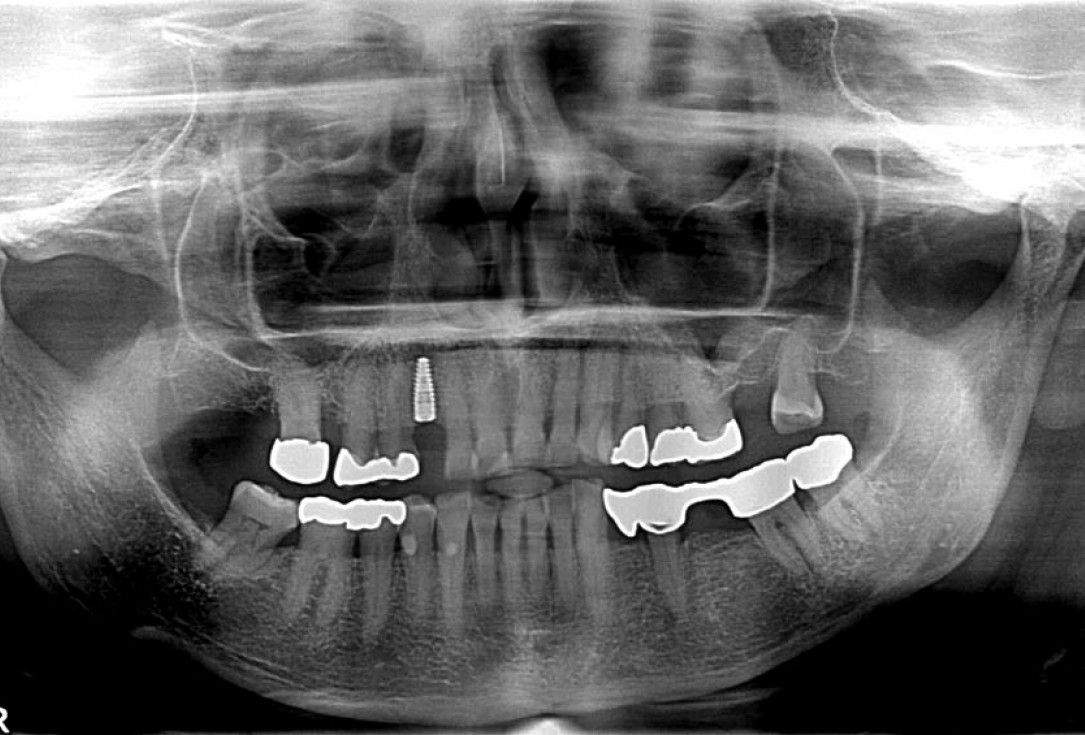

10/12 - X-ray scan after implant placement

Block augmentation with maxgraft® in the maxilla - PD Dr. Dr. F. Kloss